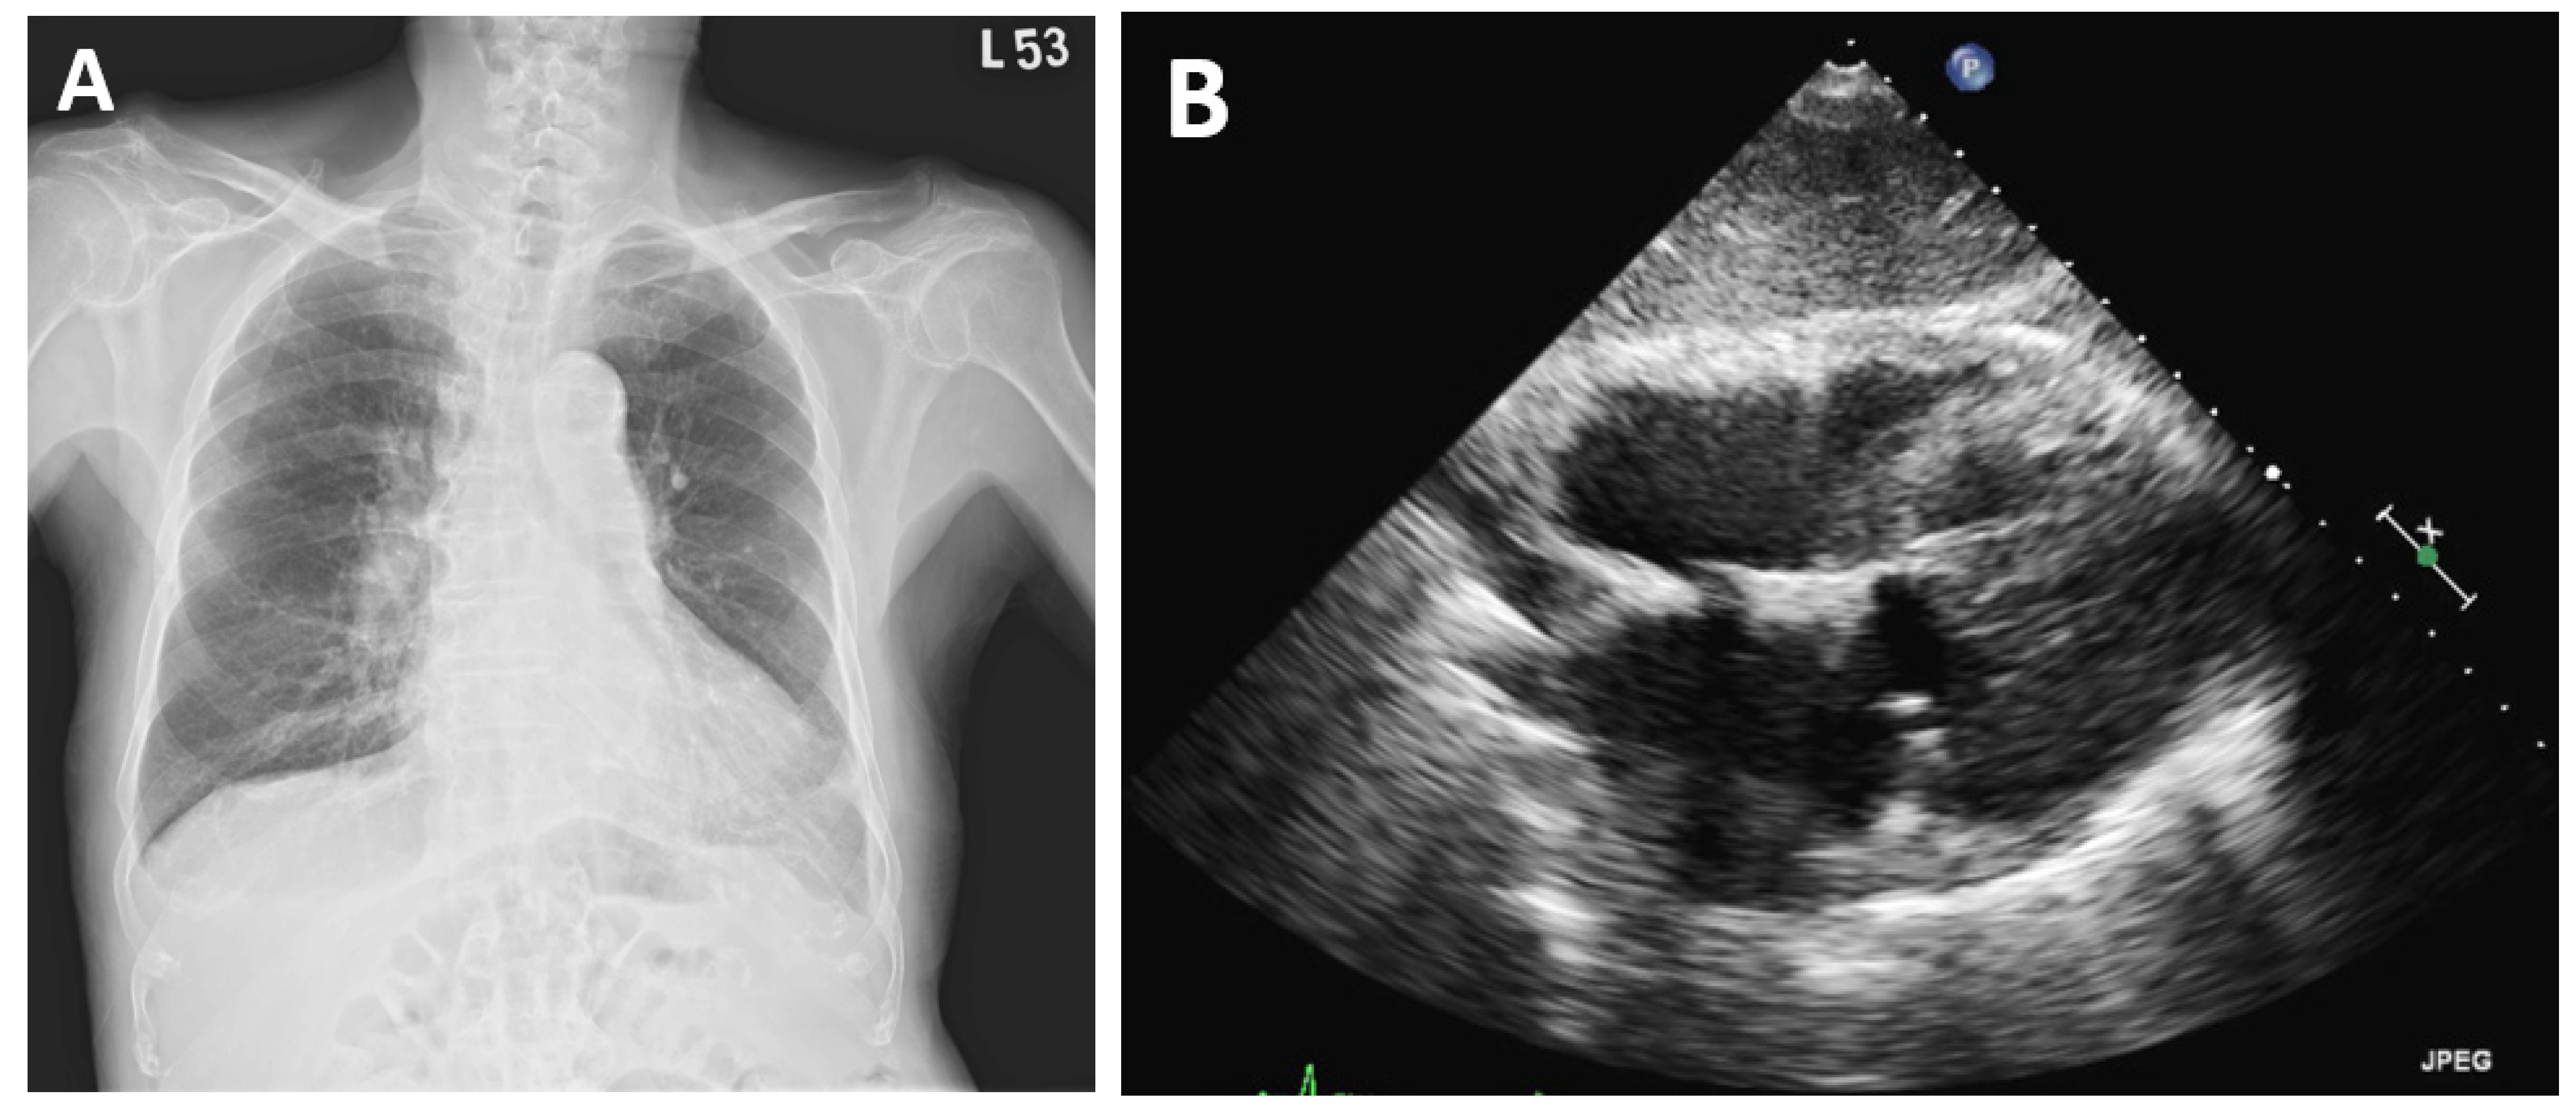

2. Case Presentation